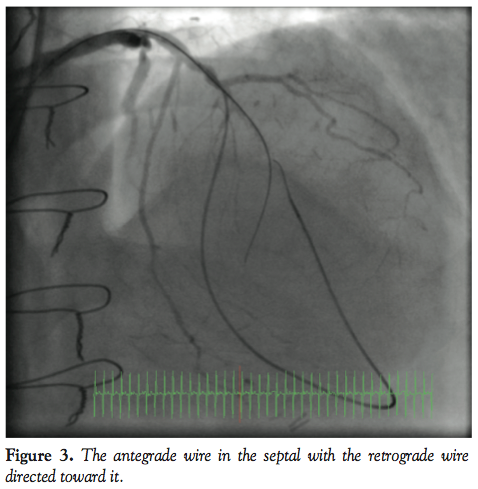

Angiogram showed the LAD occlusion in the mid course with a septal collateral filling the distal LAD retrogradely (Figure 1). An angioplasty Sion wire with a Corsair catheter (Asahi Intecc Co Ltd) was introduced into the LAD and the septal collateral and distal LAD retrogradely and a Confianza Pro12 (Asahi Intecc) antegradely through the proximal occlusion cap (Figure 2). The anterograde wire was passed into a septal branch, which gave a road map for the retrograde wire. The retrograde Sion wire was exchanged for a Pilot 200 wire (Abbott) which was navigated retrogradely (Figure 3) and crossed the proximal occlusion cap followed by the Corsair catheter (Figure 4). Following that, a 300 cm RG3